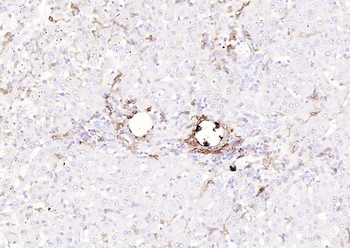

| Tested applications | IHC |

| Dilution range | Immunohistochemistry (Frozen & Formalin-fixed) (1-2ug/ml for 30 minutes at RT),(Staining of formalin-fixed tissues is enhanced by boiling tissue sections in 10mM Citrate Buffer, pH 6.0, for 10-20 min followed by cooling at RT for 20 minutes),Optimal dilution for a specific application should be determined. |

| Application notes | Positive Control: Human tonsil or lymph node |